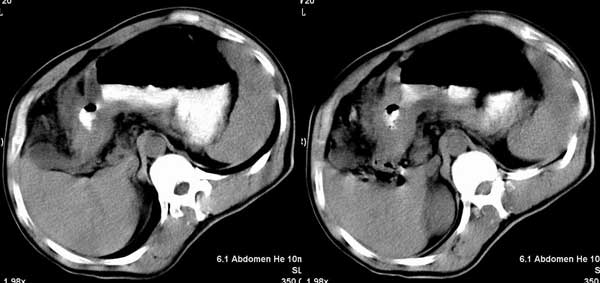

以下是引用听蝉观竹在2005-2-15 23:30:28的发言:[br]胃窦癌。[br]建议做胃镜检查并活检。

以下是引用大鹏在2005-2-16 16:14:44的发言:[br]我院用俯卧位显示胃窦部效果很好.[em4][emb26]